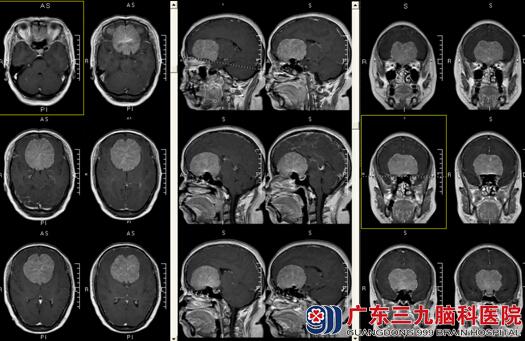

今年57岁的程阿姨,因“头痛伴视物模糊、多尿半年,加重1周”来医院就诊。入院后查体:神志清楚,精神差,言语缓慢,思维迟缓,记忆力下降。查体可配合。辅助检查:前颅窝底大脑镰两旁巨大占位性病变,考虑脑膜瘤可能性大;MRV检查提示:上矢状窦额部显影浅淡,额部静脉分支增多。CTA:前颅窝底巨大软组织肿块,供血极其丰富,邻近双侧大脑前动脉及分支明显受压向上移位,其中A1-A2段部分主干及额极动脉被包绕。入院诊断:前颅窝底巨大脑膜瘤。

完善术前准备后,有林涛主任主刀在全麻下行“鞍结节巨大脑膜瘤切除术”,手术顺利,术中肿瘤全切除。术后程阿姨恢复良好,精神好,言语可,记忆力明显改善,无头晕头痛、肢体抽搐,电解质正常,双眼视力明显恢复,左眼视力4.6,右眼视力4.2。四肢肢体肌力正常。术后病理提示:脑膜瘤WHOI级。